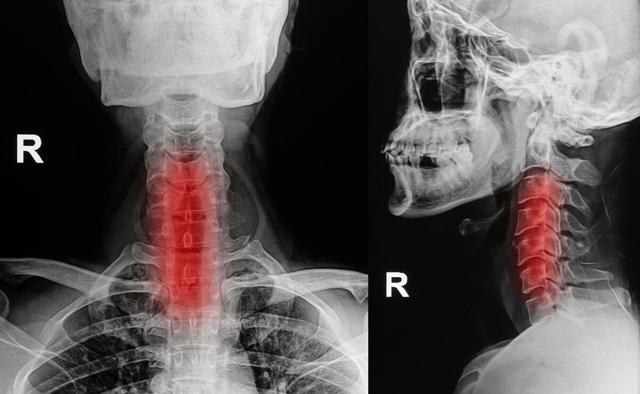

4.頚椎症

頚椎の肥大や過形成、頚椎椎間板の変性やヘルニアは、頚神経根や頚髄を圧迫し、片側または両側の手指のしびれや痛みを誘発し、それが次第に上腕や前腕に進展し、上肢の運動障害にまで至ることがある。

如中高年特に指先のしびれ。夜間就寝中に悪化する多くは頚椎症が原因である。頚椎症は中高年に多い。骨棘頚椎症の場合、夜寝ている間に肥大した骨によって頚椎神経が圧迫刺激を受け、それが症状を引き起こす。

頚椎症による指先のしびれは、以下のような症状で現れることが多い。発作が続くのステータスを維持することが推奨される。頸椎レントゲン、頸椎MRIなど。さらに原因を特定するための検査。

1.頚椎症

頚椎症患者の種類によっては、指先のしびれも考えられる症状の一つですが、頚椎症患者は指先のしびれ以外にも、上肢や下肢の脱力感、首の後ろの痛み、歩行困難、耳鳴り、首の重苦しさ、めまい、吐き気などの症状を伴うことがあります。頚椎症の診断は難しくなく、整形外科に行ってレントゲン検査をすれば、はっきりした診断がつくかもしれません。

頚椎症 頚椎症

右手のしびれ、神経圧迫症状による頚椎症圧迫の場合は、理学療法マッサージマッサージを行うことをお勧めし、コンピュータの前での長時間の作業、運転などに従事することを禁止し、血圧検査を行うために病院に行くことである状況がある高血圧はなく、頭痛やめまいはありません。

頚椎症、骨棘、椎間板ヘルニアなどは、脊髄から枝分かれする神経根が詰まりやすく、詰まると手のしびれも起こり、手のしびれは胸郭出口症候群と同じような症状が現れます。しかし、手のしびれによって引き起こされるこの症状は、より明らかな頚椎の不快感、こわばり、痛み、活動制限があるでしょう。

頚椎に問題がある場合、腕神経叢の神経が圧迫されると、手のしびれや手の痛みが生じ、脳への血液供給が不足し、めまいや吐き気を引き起こす深刻な引き金となります。頚椎症による手のしびれは、親指と人差し指のしびれ、小指と薬指のしびれなど、主に片側のしびれとして現れ、ボタンが結びにくい、箸が持ちにくいなど、指の柔軟性が失われます。頚椎症になると、手指のしびれだけでなく、頚部や肩の筋肉痛、上肢の放散痛などを伴うようになります。そのため、片側の手のしびれの症状が出たときには、頚椎症かどうかを警戒する必要があります。

5.頚椎症

頚椎症は頚椎が突出する長期的な要因により、両側の神経や血管を圧迫し、指のしびれの主な原因は神経から腕神経叢神経や頚神経を圧迫することであるため、腕神経叢神経損傷や頚神経叢神経損傷だけでなく、上肢の神経の損傷も指のしびれの原因となります。